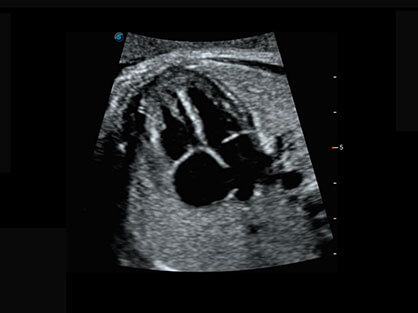

通过对组织运动信息、血流信号及背景噪声进行准确智能的阈值判定,高效提取出微弱血流信号,获得高灵敏度和空间分辨率的血流图像,为临床提供更加真实和丰富的诊断信息。

0.5mm厚度的薄层切片显像,可清晰显示微小病灶的连续断面。